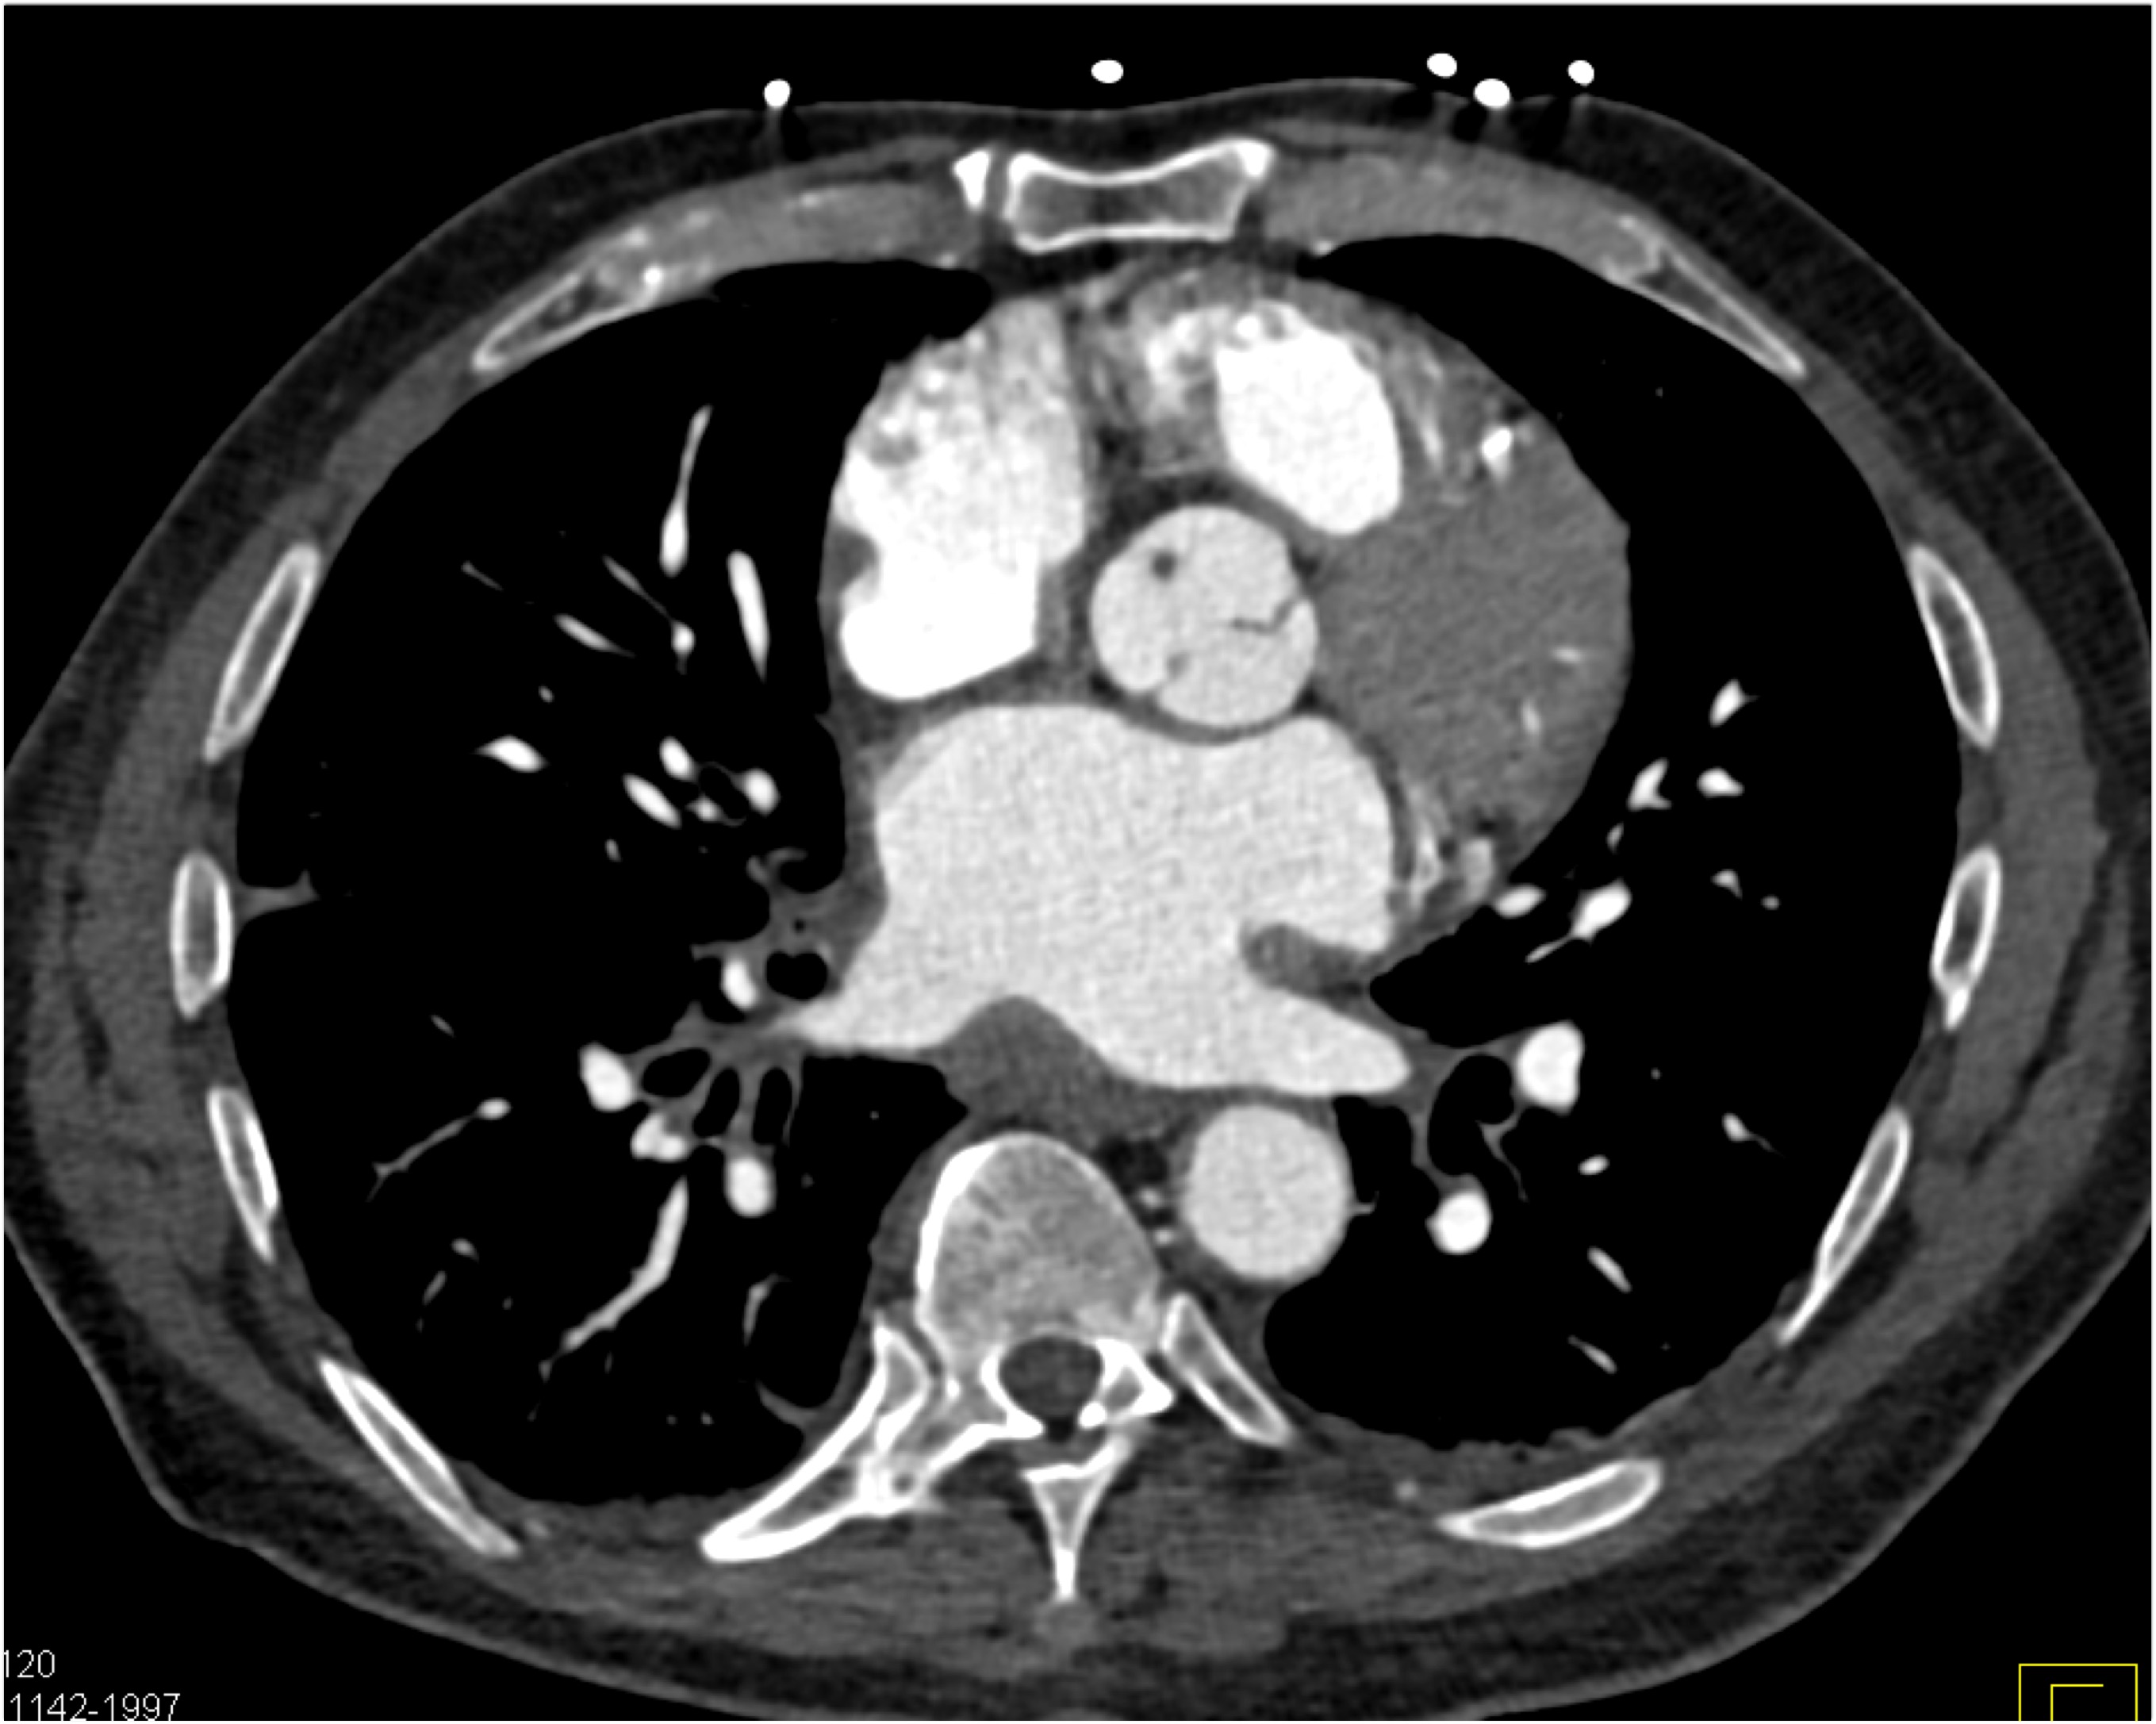

6) The most likely diagnosis in this case is?

vegetations in pulmonary valve

failed pulmonic valve

normal appearance of repaired pulmonary valve

abscess of the pulmonary artery